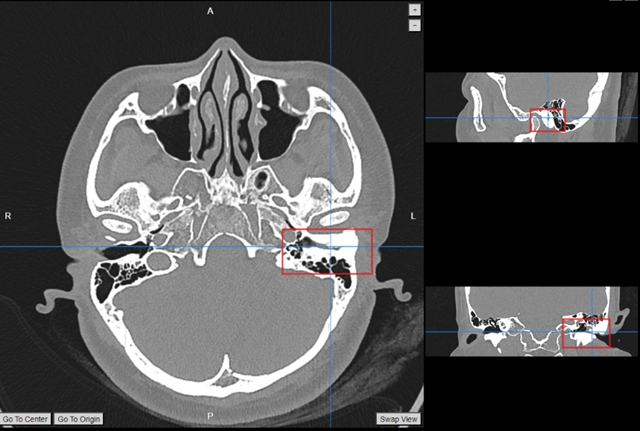

투득시 병원에서 드문 외이도 골증식증 수술이 성공적으로 이루어져 환자가 정상 청력을 회복했다.